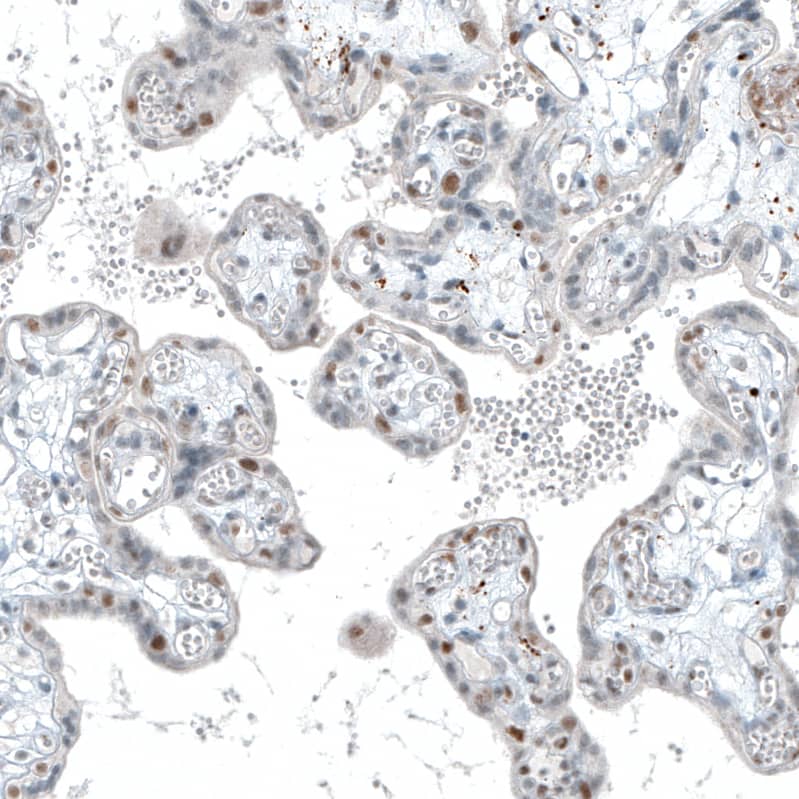

TET2 Antibody - BSA Free

NBP2-32104

WB, IHC, IP

Host:

Rabbit Polyclonal